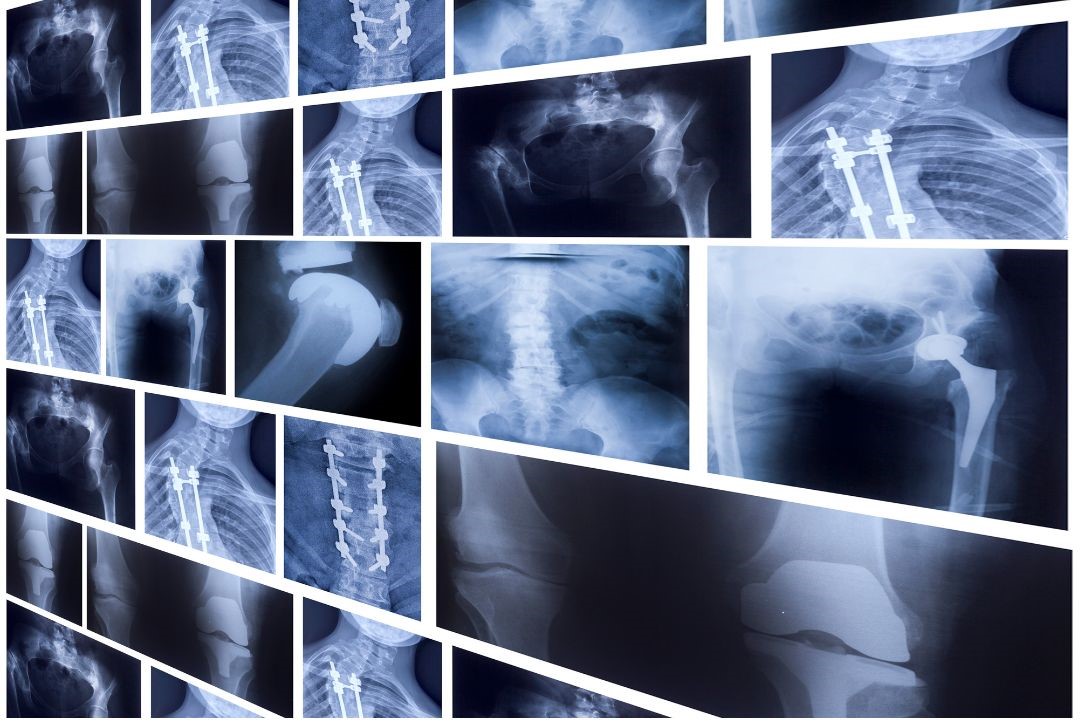

An x-ray is a simple and effective imaging tool used to assess the structure of bones and joints. It can identify issues such as fractures, degeneration, arthritis and spinal alignment problems. For many musculoskeletal conditions, an x-ray provides the clarity needed to understand what is happening beneath the surface. Chiropractors often use x-rays to guide safe and accurate treatment plans, ensuring that any underlying structural concerns are clearly identified.